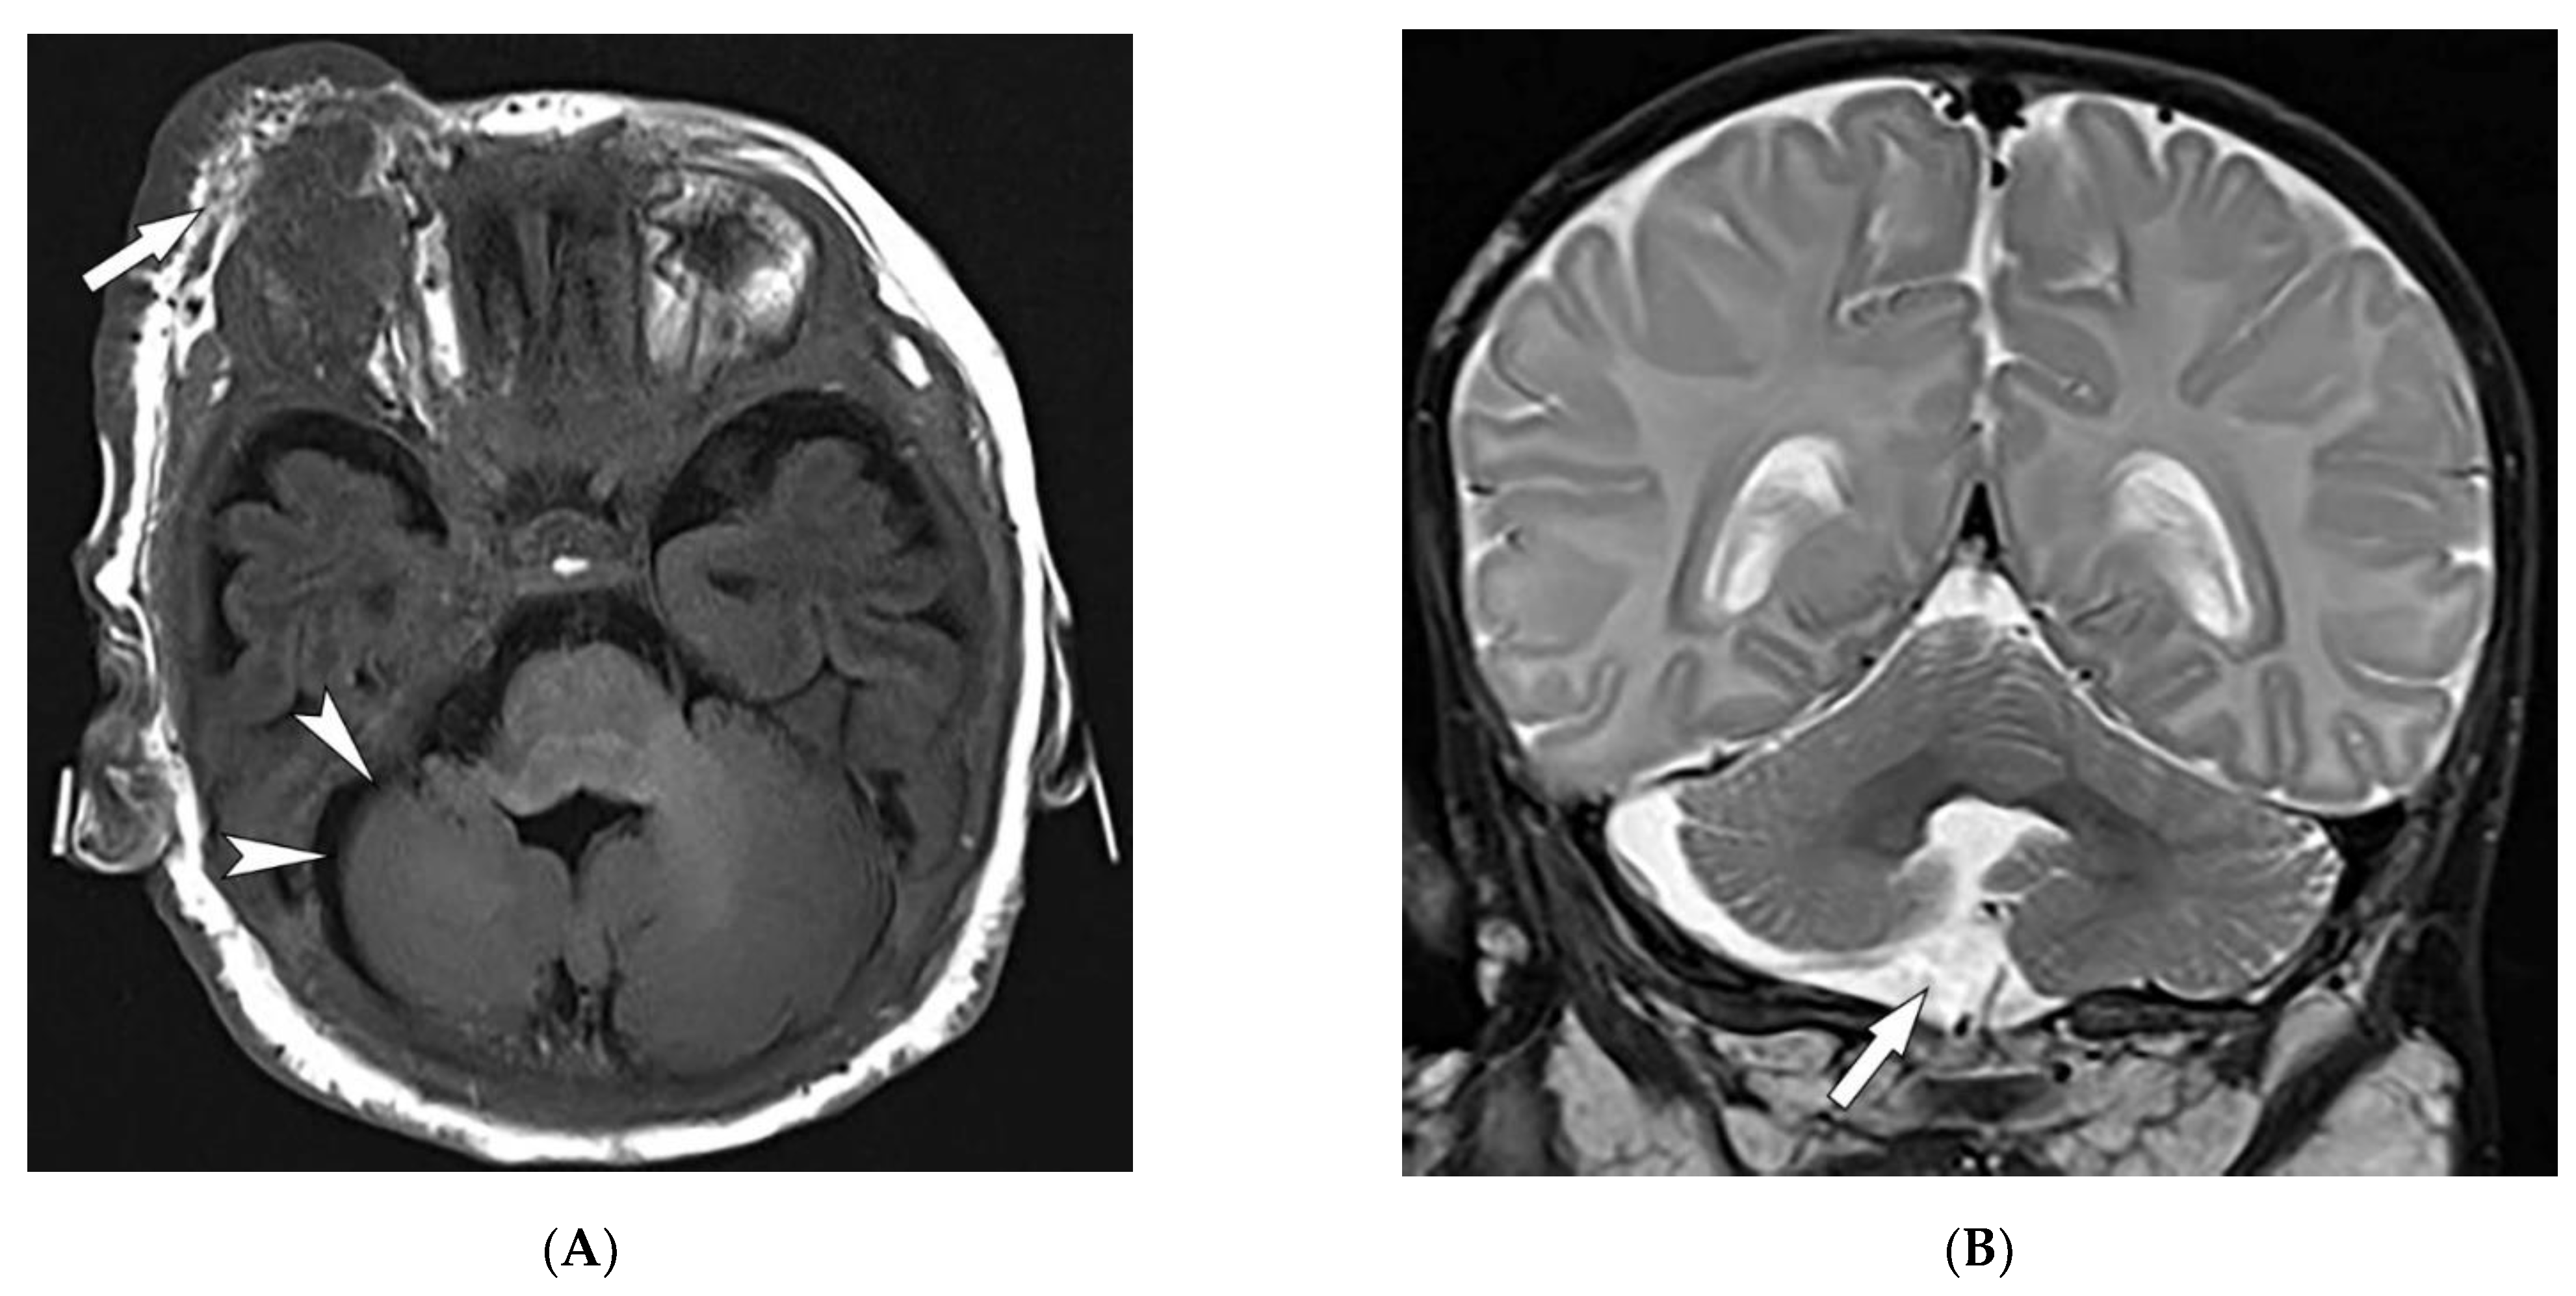

| Behcet’s disease | Oral and genital ulcers Ocular findings Vasculitis CNS lesions | Thickening of the aorta and SVC Bilateral pulmonary artery aneurysms Basal ganglia and brainstem lesions |

| Sturge–Weber syndrome | Port-wine stains Leptomeningeal capillary malformation Glaucoma | Parieto-occipital cortical hemiatrophy Tram-track calcification Calvarial thickening |